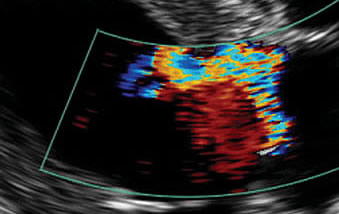

In imaging the heart, ultrasound is at its best, as the heart is a fluid filled organ. Abnormalities such as diseased heart muscle (hypertrophic and dilated cardiomyopathy), fluid around the heart (pericardial effusion), and congenital abnormalities can be diagnosed and their severity can be assessed. Heart-base tumors, which are rarely visible on radiographs, are easily visualized with ultrasonography.